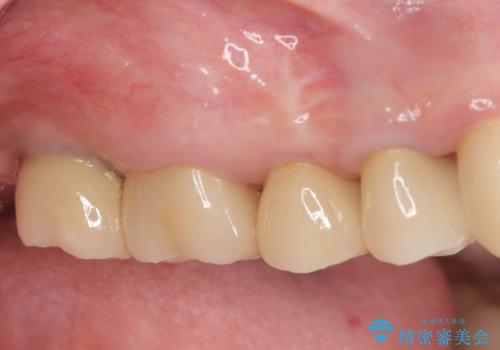

[ 破折し大きく吸収した歯槽骨 ] 他院では難しいと言われたインプラント治療

![[ 破折し大きく吸収した歯槽骨 ] 他院では難しいと言われたインプラント治療の症例 治療後](https://seimitsushinbi.jp/wp/wp-content/uploads/2024/10/7e00d9287463e80cbc3d4b87784b3d86-500x350.jpg?v=1729760167)